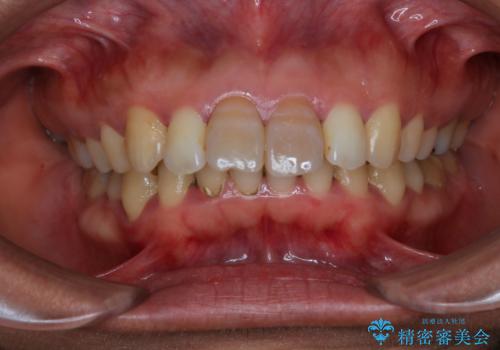

- 前歯の色が気になるとのことでご相談にいらした患者様です。診断の結果、前歯は2本とも失活していたために精密根管治療から治療を開始しました。根管治療後にウォーキングブリーチを行うことで歯の色をトーンアップさせました。患者様より周囲の歯も全体的に白くしたいとのご希望があったため、オフィスホワイトニングも併せて行いました。

ウォーキングブリーチ法とは歯の中に薬剤を入れて内側からホワイトニングを行う方法であるため、根管治療がされている歯のみ適応となります。生活歯(神経が生きている歯)に対してはオフィスホワイトニングやホームホワイトニングが有効です。